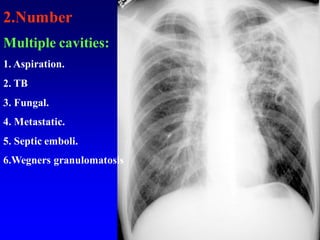

2.Number

Multiple cavities:

1. Aspiration.

2. TB

3. Fungal.

4. Metastatic.

5. Septic emboli.

6.Wegners granulomatosis